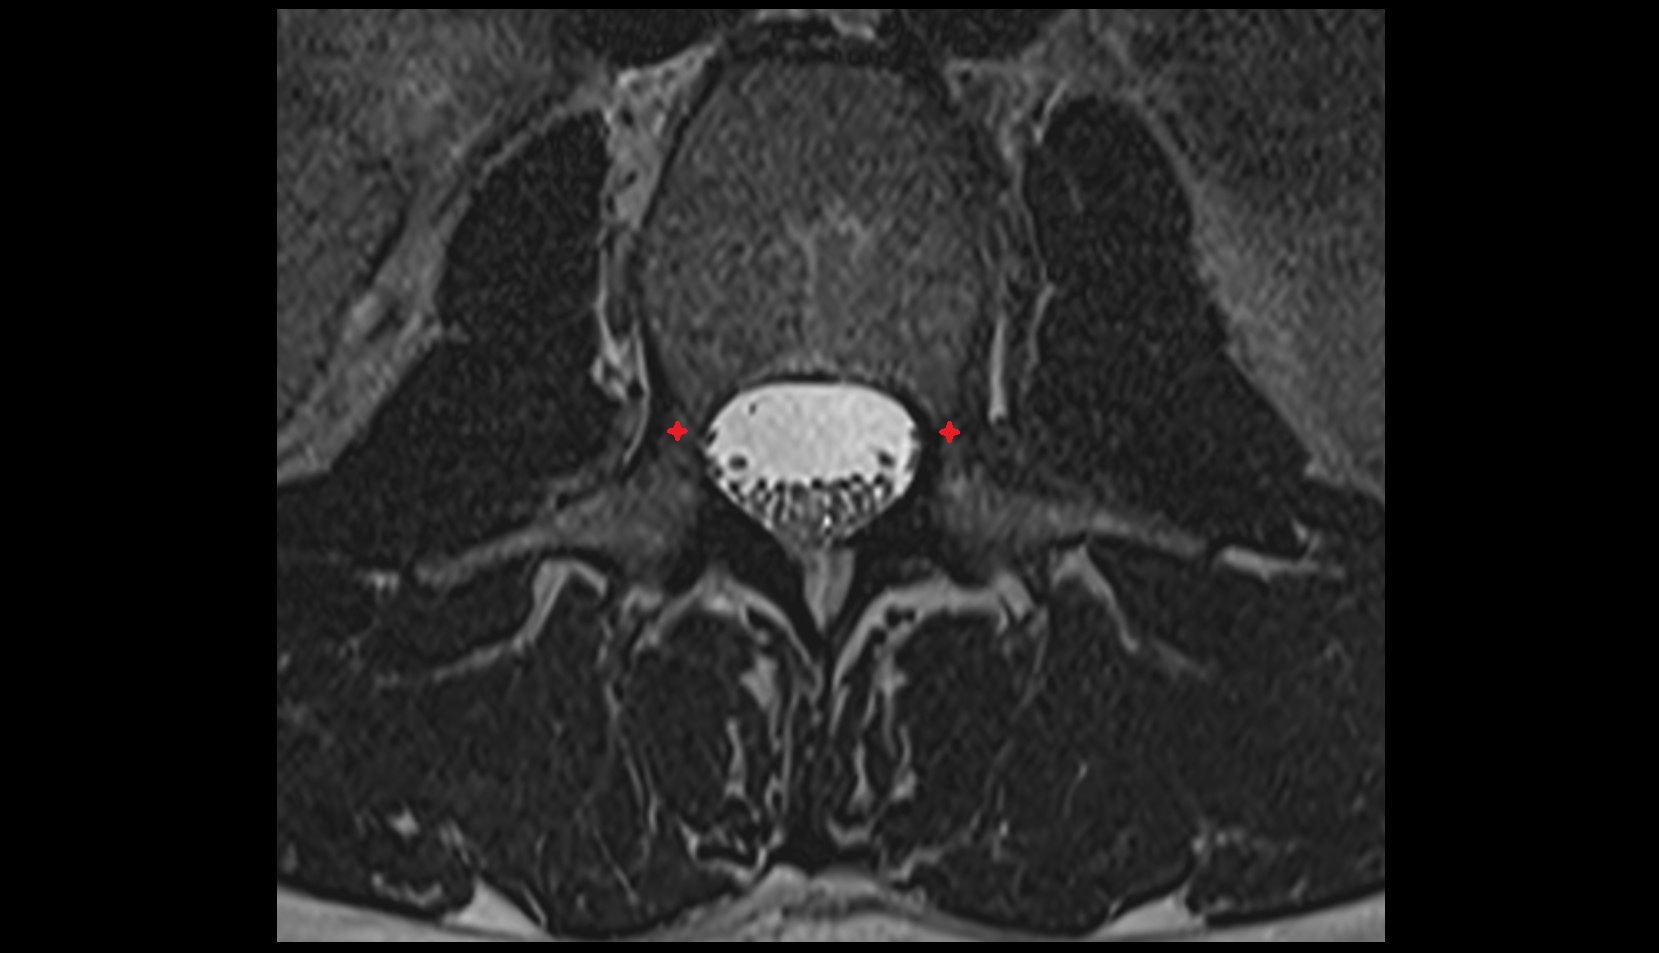

- Annulus fibrosus of intervertebral disc

- Spinal dura mater

- Spinal epidural space

- Cauda equina

- Conus medullaris